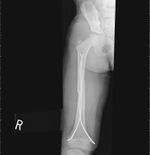

He was treated by flexible retrograde intramedullary rods with closed insertion under image guidance with good pos-top results.

His rods will be removed at three months and he is expected to make a full recovery.